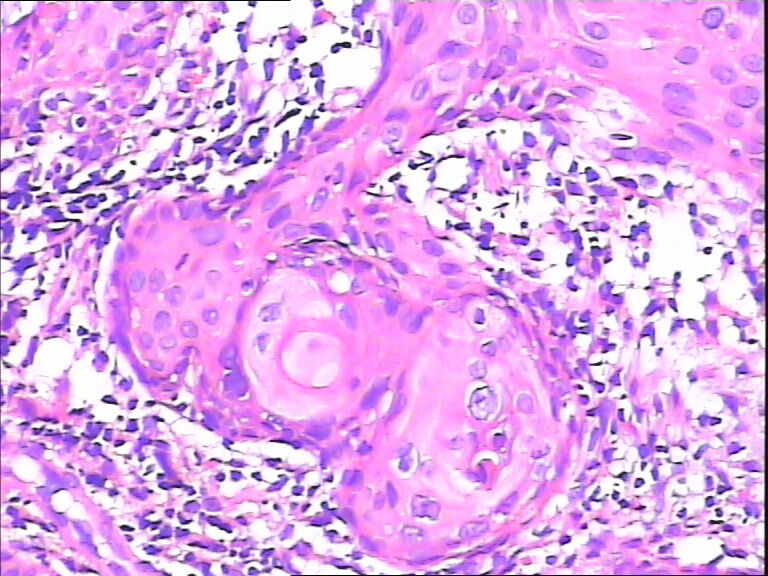

45y,触血,宫颈多点活检。

考虑HPV感染,应该没有高级别上皮内瘤变,建议做HPV检测。

CINⅡ,提示HPV感染。

慢性宫颈炎伴HPV感染改变、腺体鳞状化生。

湿疣改变

HPV感染。局部已达到CIN2-3

主要考虑HPV感染引起的细胞改变。

HPV感染。灶性CIN2-3

HPV感染

不同级别的CIN,局灶已达到CIN3。

HSIL伴